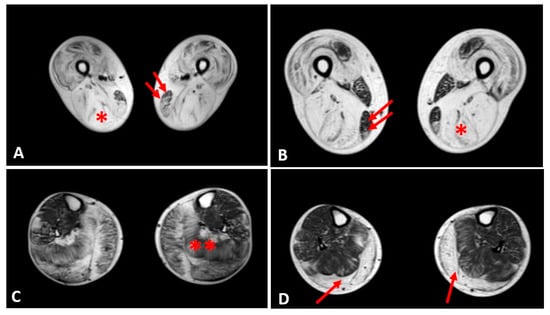

3.4. Muscle MRI Changes